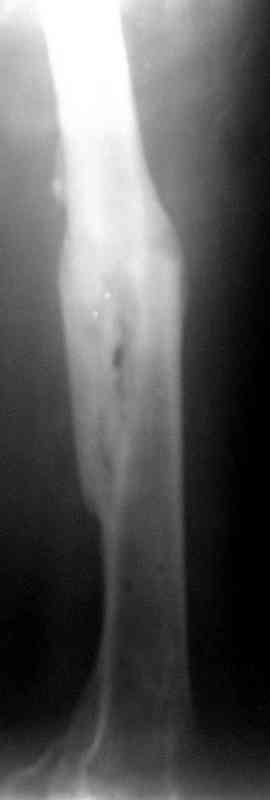

месяцев дистракции укорочение левого бедра удалось полностью устранить. 22.02.00, т.е. через 2 месяца после повторного остеосинтеза, больному произведено дистальное блокирование штифта двумя винтами и демонтирован аппарат Илизарова. В течение 2 недель после операции больной ходил с помощью костылей, потом 2 недели с тростью. Опороспособность и функция оперированной конечности полностью восстановились через 4 недели после операции.

Фиксаторы удалены через 12 месяцев после операции, выполненной по поводу замедленной консолидации перелома бедра с его укорочением.